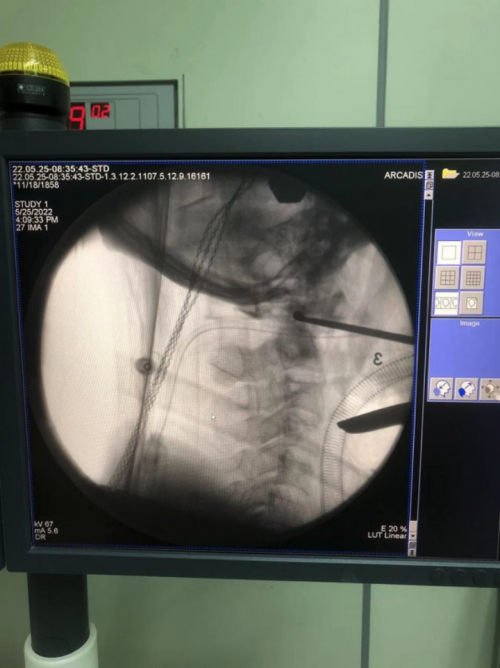

近期,附一医院脊柱外科许卫红教授团队在鼻内镜辅助下为患者进行经口松解。在耳鼻喉科林功标教授团队、麻醉团队的共同协作下,许卫红教授首先在鼻内镜下用等离子刀和磨钻为该患者完成经口寰枢关节松解,随后再经后路行寰枢椎复位内固定术,这样充分松解了寰枢关节,取得了寰枢椎的解剖复位,脊髓压迫完全解除。

图片

医生在手术中